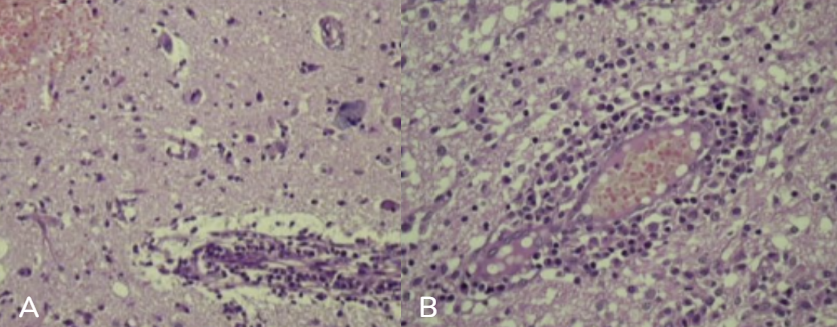

| Histopathology | |

![]() | ํ๊ด ์ฃผ๋ณ์ผ๋ก lymphocyte ์นจ์ค๋์ด ์์. (Immune-mediated) |

![]() GME case์ histopathology | - A : perivascular cuffings (ํ๊ด ์ฃผ๋ณ์ผ๋ก ๊ฒ๊ฒ ๋ ๋ถ๋ถ๋ค์ด ๋ง์) - B : lymphoid cells ์นจ์ค (ํ๊ด ๋ด ํ์ ๊ณตํฌ๋ก ๋ํ๋๋ ์ง๋ฐฉ ๊ตฌ์กฐ๊ฐ ํฌ๋์ ๊ฐ์ด ํ๊ด์ ์ธ๊ณ ์์.) |